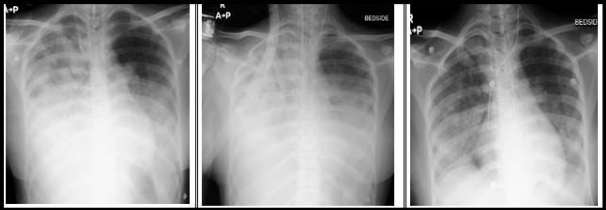

27 year old female came with complaints of breathlessness and dry cough increased since 3 to 4 days. She also had history of ankle joint pain and asymmetrical swelling. She was recently admitted with membranous tonsillitis in an outside hospital and was treated with iv antibiotics. She also had a history of chronic iron deficiency which was evaluated with colonoscopy which showed terminal ileal ulcers. She was admitted in Aster RV hospital with the above mentioned complaints, she was not hypoxic at the time of admission and her vitals were stable. CT chest was done which showed diffuse patchy ground glassing in bilateral lung fields with relative sparing of the sub pleural zones predominantly involving lower lobes. Few nodular infiltrates and fibrotic foci in the left upper lobe also seen. Differentials included atypical viral pneumonia and rheumatoid lung. She was started on IV empirical antibiotics, antivirals and other supportive measures. The next day she became hypoxic with spo2 dropped to 89% on room air and she was started on supplemental oxygen. Hence fibreoptic bronchoscopy was done and lavage taken from both the lower lobes. Bronchoscopy showed haemorrhage in the tracheobronchial tree as shown in figure 1A. Indicative of DAH. Sequential BAL collected also indicated DAH. BAL samples were negative for Gene Xpert MTB/RIF, AFB smear , KOH mount and aerobic culture showed no growth . Since bronchoscopy showed a picture of intra alveolar haemorrhage , her connective tissue work up was done which showed PM scl 75, ANCA PR3 ( C ANCA ) were positive. Her Blood and urine cultures showed no growth. She dramatically worsened in a day and was intubated and started on mechanical ventilation in view of persistent hypoxia and low PaO2/FiO2 . She was put on volume controlled ventilation , Tidal volume 400 ml , PEEP- 6 cmH2o, Respiratory rate of 18 breaths / min were applied. Despite the continuous mechanical ventilation with a fio2 of 100 % , hypoxemia failed to improve and Pao2/ Fio2 continued to deteriorate. However she didn’t improve and had persistent hypoxia with hypercarbia despite maximum ventilator support. After detailed discussion she was initiated on Extra corporeal membrane oxygenation (ECMO) on Day 4 of hospitalisation after getting informed consent and explaining the risks and complications of the procedure. A 22 Fr cannula was inserted into the patients right femoral vein and 16 Fr cannula was inserted into the patient’s right jugular vein . The location of the cannulas were confirmed by the Trans Oeosophageal Echo (TEE) . The blood was then circulated from the femoral vein to the oxygenator and then to the internal jugular vein . The blood flow rate was started at 3.5 litres / min and sweep gas flow was set at 7 litres / min . She was given bolus of 5000 IU of heparin during ECMO initiation and then started maintainance dose of 1000 units per hour after 2 hours . Her ACT was checked every 6 hours and maintained around 180 and APTT was maintained around 60 seconds . Since BAL samples were negative for any infective foci , diagnosis of DAH was considered and she was given 3 doses pulse methylprednisolone 1gm/day .

Figure 2: Fibreoptic Bronchoscopy image of DAH